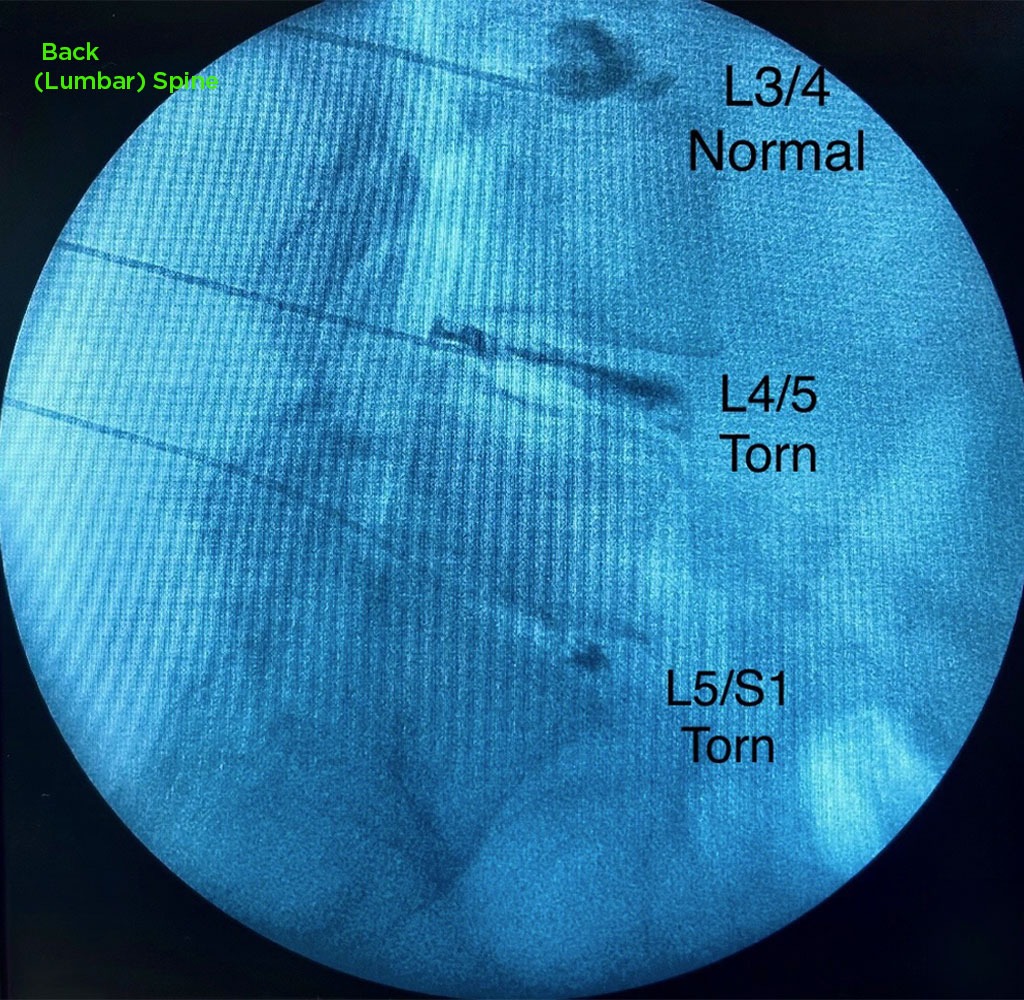

Annulargram™ Gallery

This gallery contains Annulargram images.

The Annulargram is a pain-free test and a crucial part of the DISCSEEL Procedure that identifies even the most subtle tears in spinal discs that MRI and discography cannot.

During the Annulargram, every disc in the region is tested to address current and future pain issues by finding even the most subtle annular tears. With the Annulargram, damaged spinal discs are pinpointed and precisely treated with Fibrin, leaving all healthy discs as they are.